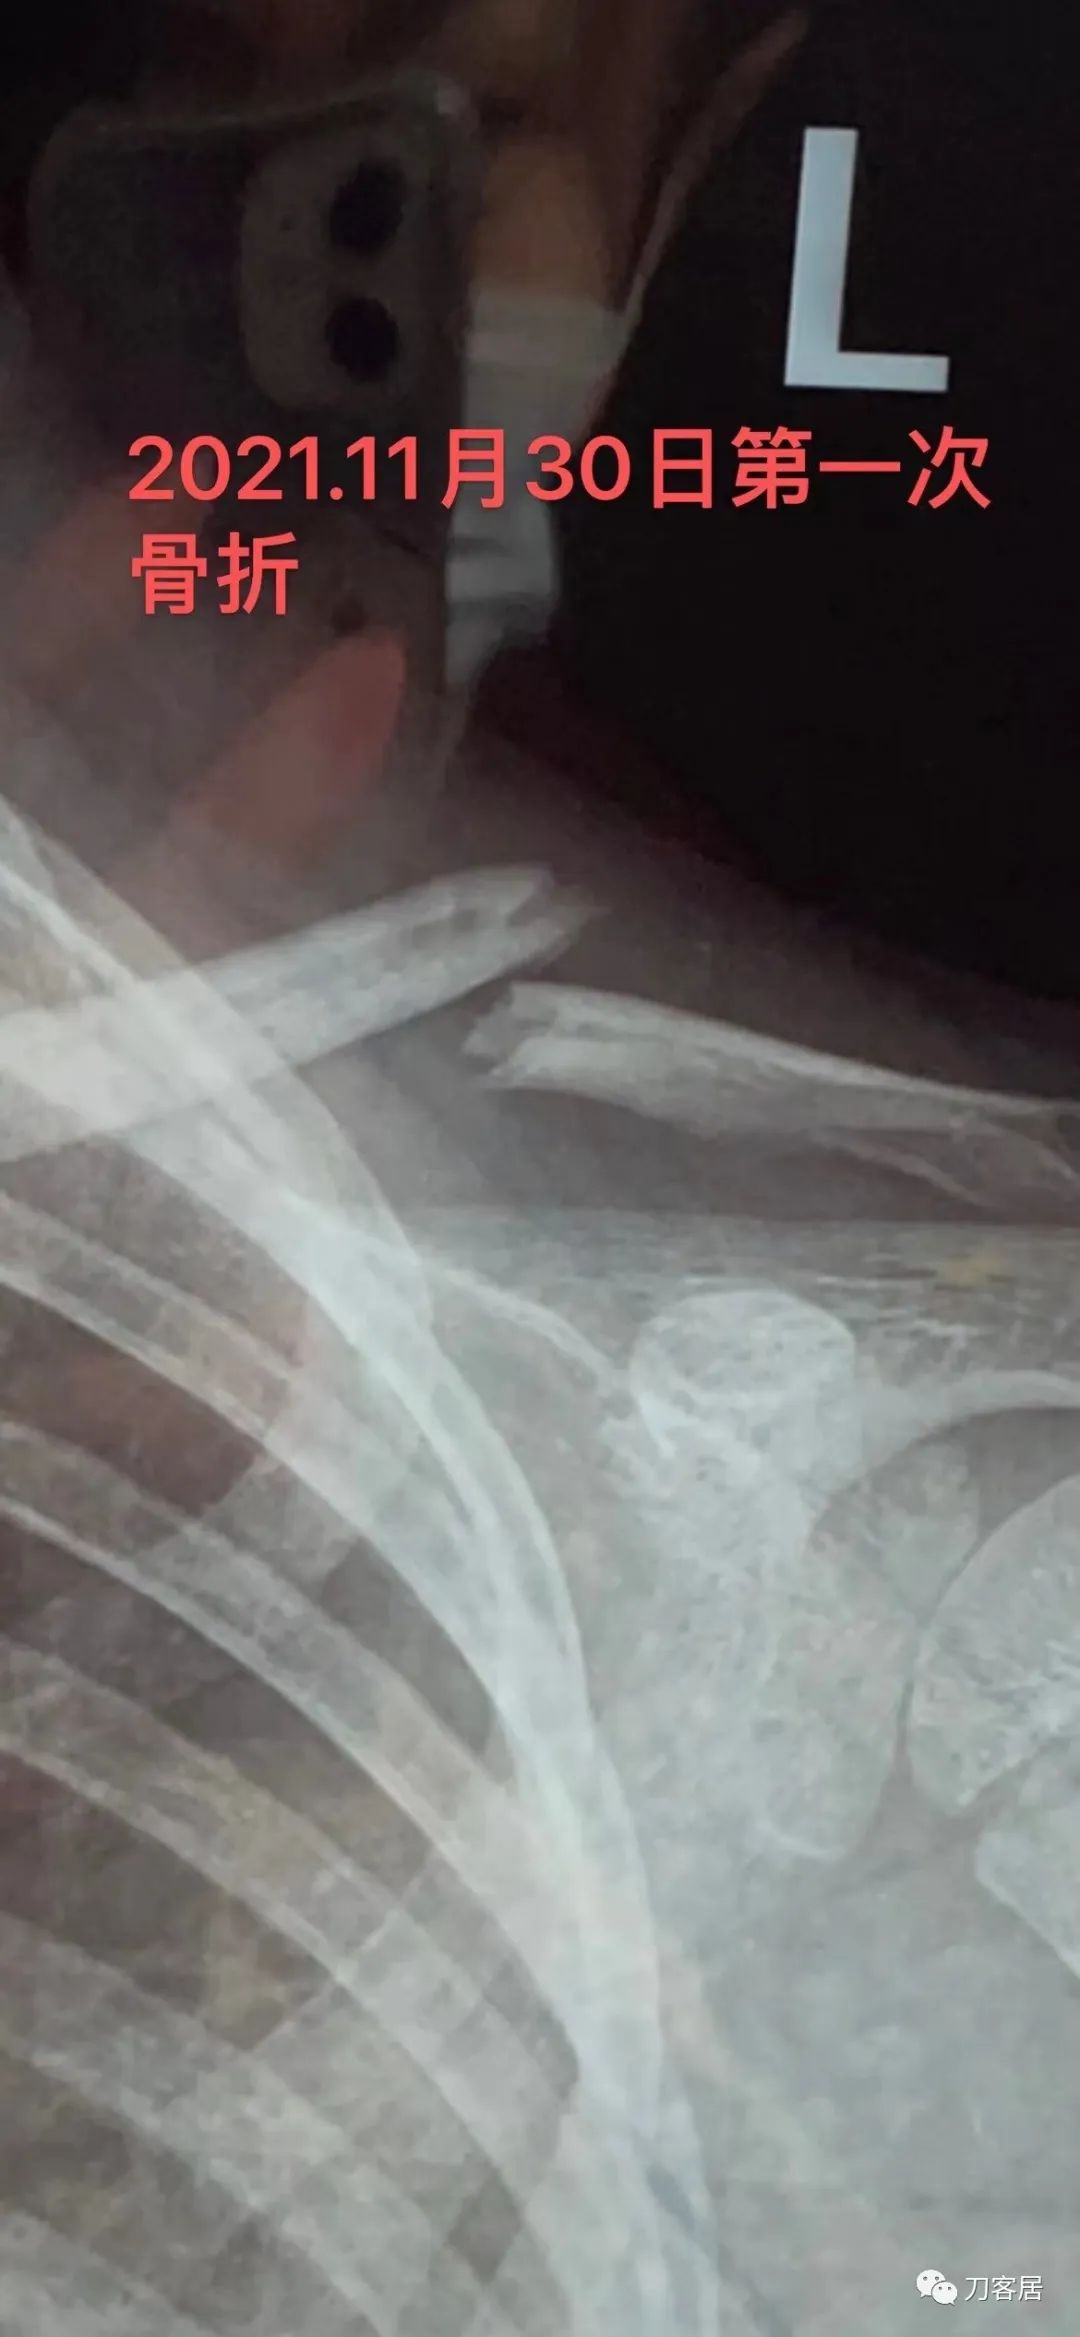

Clavicle fractures are one of the most common injuries sustained during childbirth; children of large birth weight (greater than 4,000 g) and those with shoulder dystocia are at the highest risk. Infants who sustain a clavicle fracture may also sustain a brachial plexus injury because of nerve stretch (Erb palsy). The neonate with a clavicle fracture may present with an asymmetric Moro reflex or the appearance of a flail upper extremity.

锁骨骨折是分娩过程中最常见的损伤之一;体重较大(大于4000克)新生儿和肩部难产新生儿发生锁骨骨折的风险最高。锁骨骨折的新生儿也可因神经牵拉而导致臂丛神经损伤(Erb麻痹)。锁骨骨折的新生儿可能出现不对称莫罗反射(新生儿的拥抱反射)或连枷上肢外观。